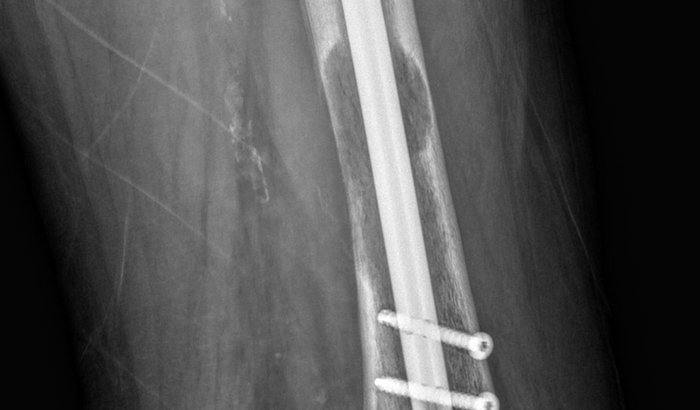

Sou a Viviane Turco e meu pai Clovis Turco está passando por um tratamento de câncer no fêmur.